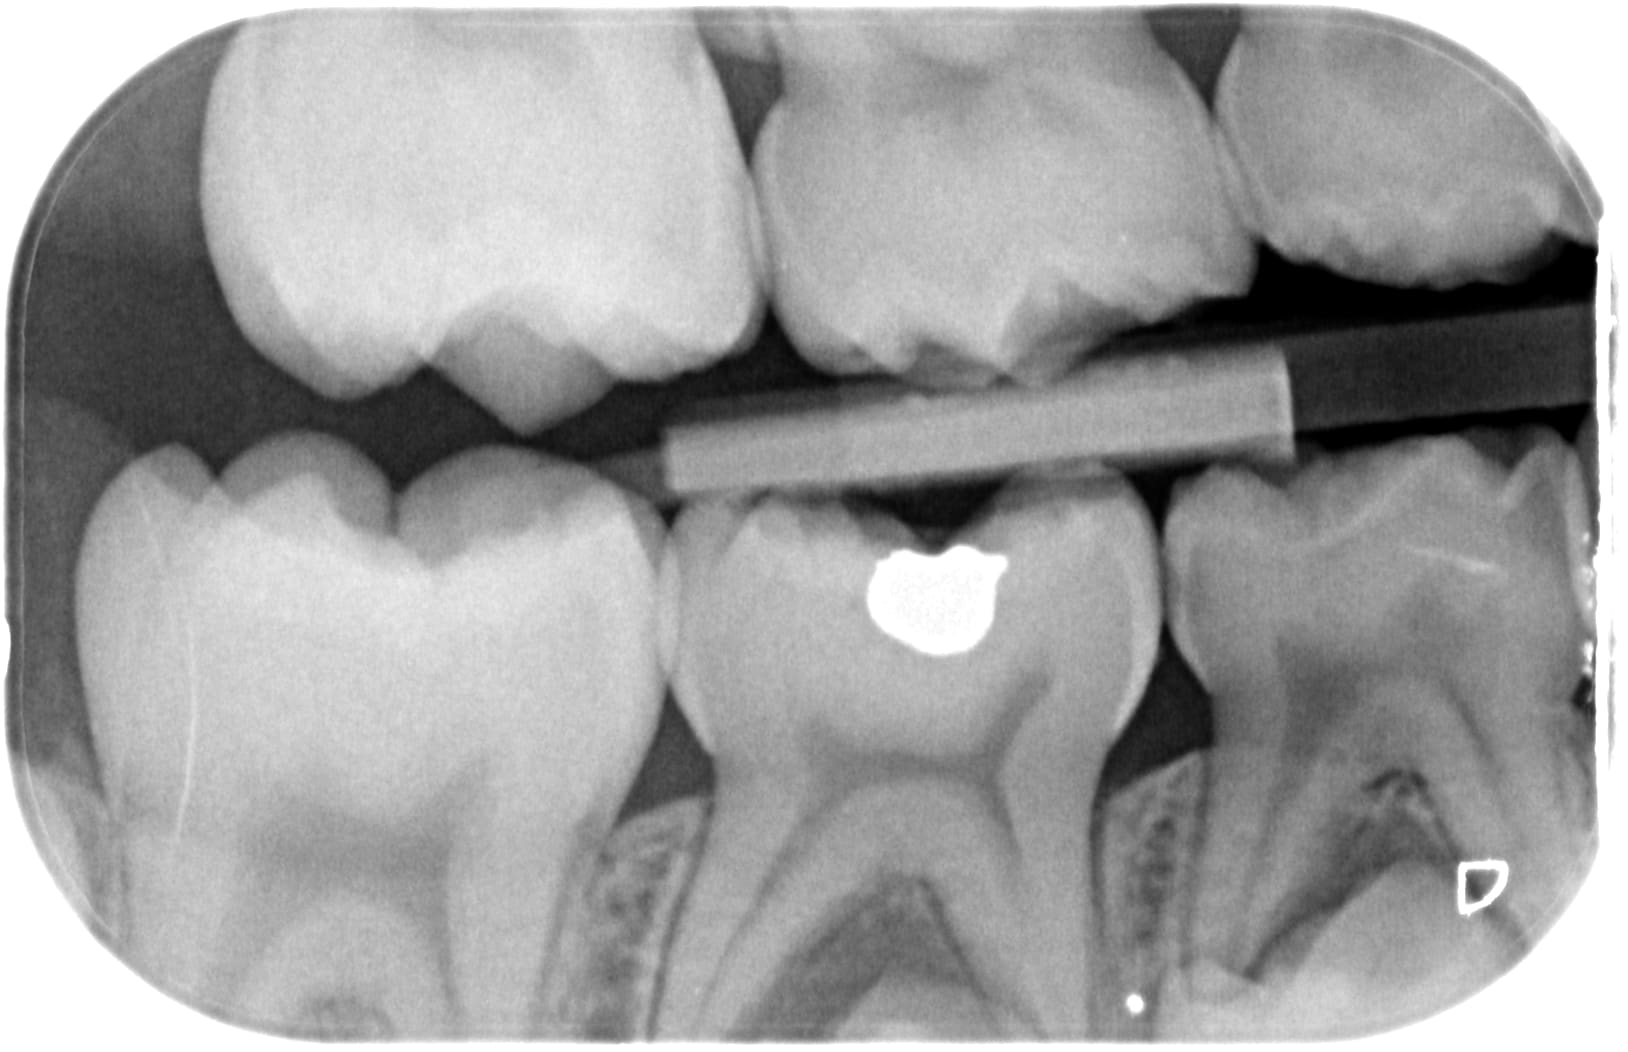

ce matin jour des enfants, je vois une jeune fille de 8ans pour la première fois...

Avant RA+10% = traitement CVIMAR des 3 caries proximales en deux séances...

Apres RA+10% = "Oh les belles dents... y'a une spicule de tartre bzim bzim... 30e, bonne journée"

t'as pas envie de ça ? on sangle et zou 8 coiffe pédo.